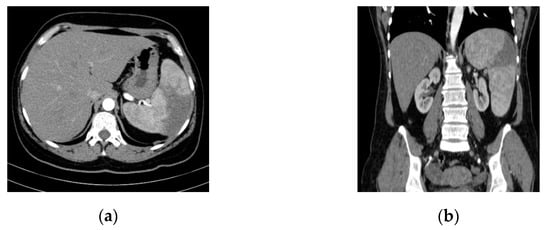

2. Case Presentation